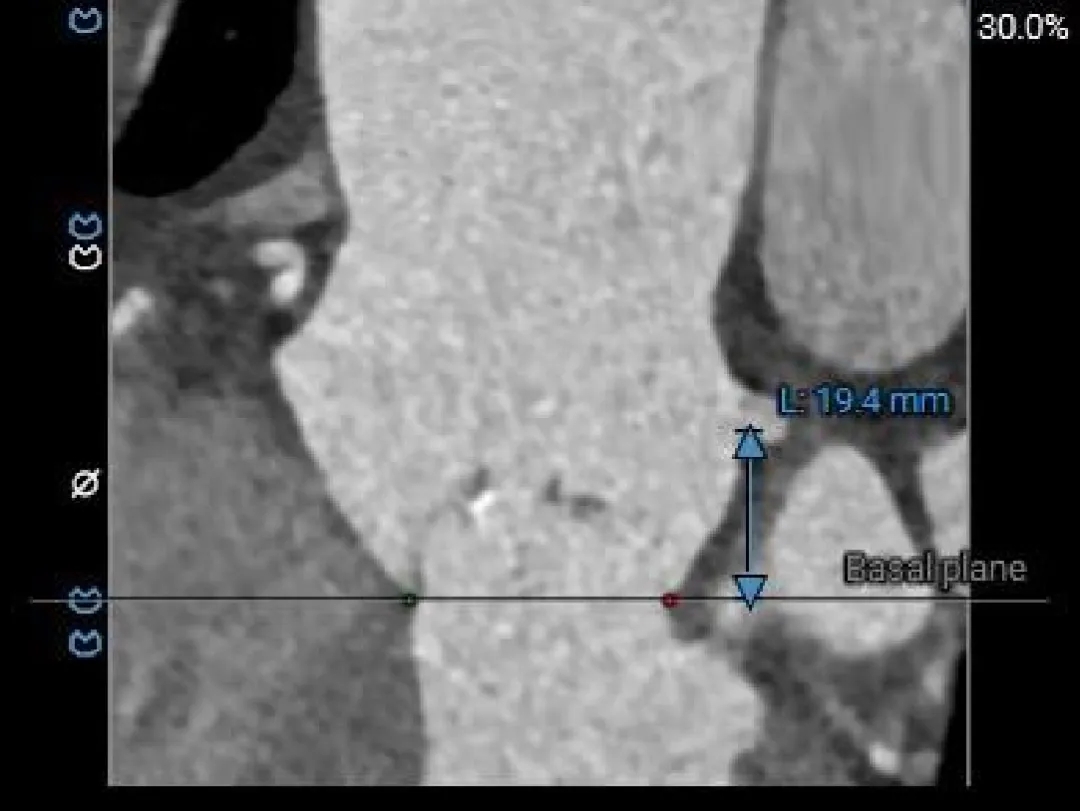

冠脉风险评估

Left Coronary

19.5mm

LCA & Leaflet

13.8mm<21.9mm

Right Coronary

18.3mm

RCA & Leaflet

17.7mm<19.7mm

左、右冠脉高度可

左右冠脉异窦

左、右冠瓣叶长度<冠脉开口下缘到窦底距离

结合SOV、STJ冠脉风险可控